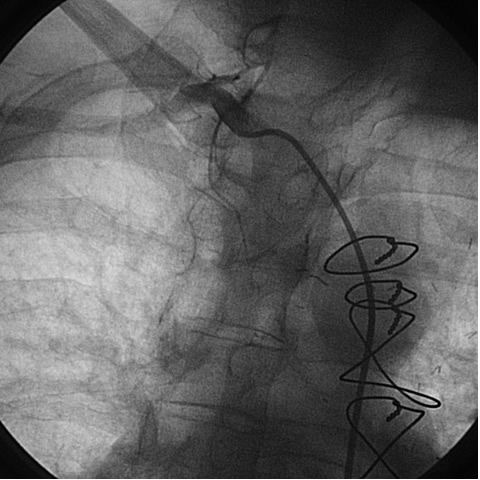

The most commonly used catheters for left heart catheterization and vein graft angiography can be seen in Figure 1 and Figure 4-13. Most of the vein grafts have horizontal take off and can be successfully engaged using a commonly used Judkins right number 4 (JR4) catheter. The JR4 catheter is the most commonly used catheter for the engagement of the right coronary ostium with horizontal take off. However, many vein grafts have unusual take off requiring different catheters. Many right coronary vein grafts have steep inferior take off making the ostial engagement with JR4 difficult or impossible (Figure 10). In such a scenario, a multipurpose catheter which has a shallow angulation is the best choice (Figure 11). The second major challenge in engaging vein graft ostia, particularly vein grafts supplying the left coronary arteries, is the shape of the aorta. A large aorta can make it very difficult for the JR4 catheter to reach the ostial vein grafts. In such a situation, Amplatz (AR) right and left (AL) catheters can be very helpful to reach the vein graft ostia. Amplatz catheters have a larger primary curve and have been used successfully in unusual superior take off of left coronary arteries or vein grafts and in large aorta. Amplatz catheters are available in different sizes (from smaller to larger curve: AR 1, AR2, AL2, AL2 and AL3). Occasionally, a very superior take off of a vein graft requires specially designed bypass graft catheters. Amplatz catheters are also extremely helpful in engaging native right coronary ostium with anterior take off.

PCI of the vein and arterial grafts have unique challenges. For any PCI, guide support is very important for successful balloon and stent delivery. In a tortuous vein graft with a steep angle, advancement of a stent can be very difficult and challenging. Therefore, it is important to choose the best available catheter before starting PCI. Similar to the right coronary angiography, a JR4 guide catheter is most commonly used in this setting. However, Amplatz guide catheters for left vein grafts and multipurpose catheters for right vein grafts are better choices in certain anatomy. In Figure 8 and Figure 10 two examples of poor guide support in two vein graft interventions can be seen. Initially, a JR4 guide was used for PCI of the vein graft supplying the left anterior descending artery (LAD) without any success. However, after changing the guide to an Amplatz left 2 guide catheter, we achieved excellent support without any difficulty in advancing two stents (Figure 9). In Figure 10, difficulty is illustrated in engaging the vein graft ostium supplying the right coronary artery with a JR4 catheter. This vein graft has a very steep inferior take off from the aorta. After changing the guide to a multipurpose catheter, we were able to deliver three stents successfully without any difficulties (Figure 11). Similar challenges exist in the treatment of the left IMA or right IMA. These arterial grafts can be extremely tortuous making stent delivery very difficult. It may be necessary to use short length stents for a better deliverability or stents with lowest profile. Usually, similar to the native coronary intervention, a 6 French guide is appropriate for the routine use.

One of the most common complication of PCI during vein graft interventions is the occurrence of “no-reflow.” After angioplasty or stenting of a vein graft, sudden cession of the distal flow could occur. This phenomenon thought to be secondary to distal embolization and platelet aggregation [2-4]. It can cause myocardial infarction, arrhythmias, hemodynamic collapse and death. It is usually treated with intra-coronary infusion of adenosine, calcium channel blockers, or nitroprusside [5-9]. After aggressive pharmacological treatment, it is usually reversible but it can be refractory causing severe myocardial damage and infarction. It usually occurs in old degenerative vein grafts or in thrombus containing lesions. However, based on the angiographic appearance, it is hard to predict which vessel is proned to this complication. There are few strategies developed in order to prevent this complication. Intra-venous glycoprotein IIb/IIIa inhibitors, which are very potent platelet aggregation inhibitors, despite success in the native coronary interventions have failed to decrease this complication in vein grafts PCI [10, 11]. On the other hand, distal filter devices have shown to significantly reduce the occurrence of this complication in vein grafts and should be routinely used if technically feasible [12-14]. A major limitation of distal filter devices is the absence of large distal vessels that can accommodate these devices and difficulty to advance such a bulky device across a high-grade lesion or across a tortuous vein graft. A recently approved proximal occlusion device has similar efficacy for the prevention of no-reflow in vein graft interventions [15]. By occluding the vein graft proximally during balloon angioplasty or stenting, flow can be stopped during stent expansion and atherosclerotic and thrombotic debris can be suctioned before the vein graft flow is restored preventing distal embolization. This technique requires lesions that are distal to the ostial vein graft and add substantial complexity and time to the procedure. Figure 2 shows the most commonly used protection devices for vein graft interventions.